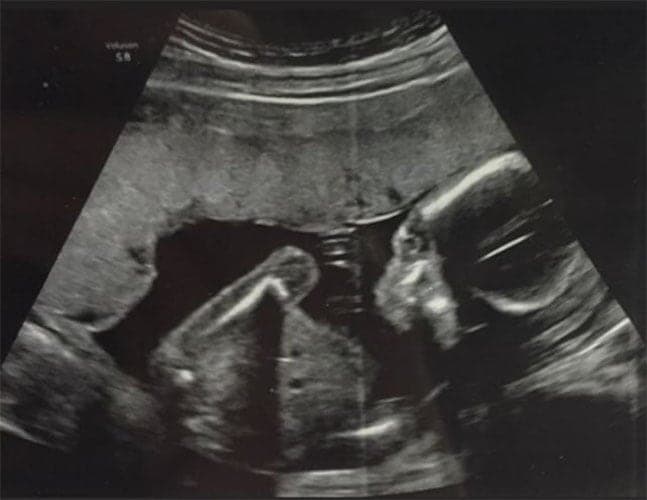

Ultraschallbilder aus dem 2. Trimester (13. bis 28. SSW)

Im 2. Trimester bekommt man oft die schönsten "Ganz-Körper" Ultraschallbilder. Das Baby ist nun so groß, dass man alles gut erkennen kann und noch nicht zu groß, so dass es noch ganz auf das Bild passt. In dieser Zeit lässt sich meist das Geschlecht bestimmen, wobei manche Babys es einfach nicht preis geben wollen und sich immer so drehen, dass man nichts erkennen kann.